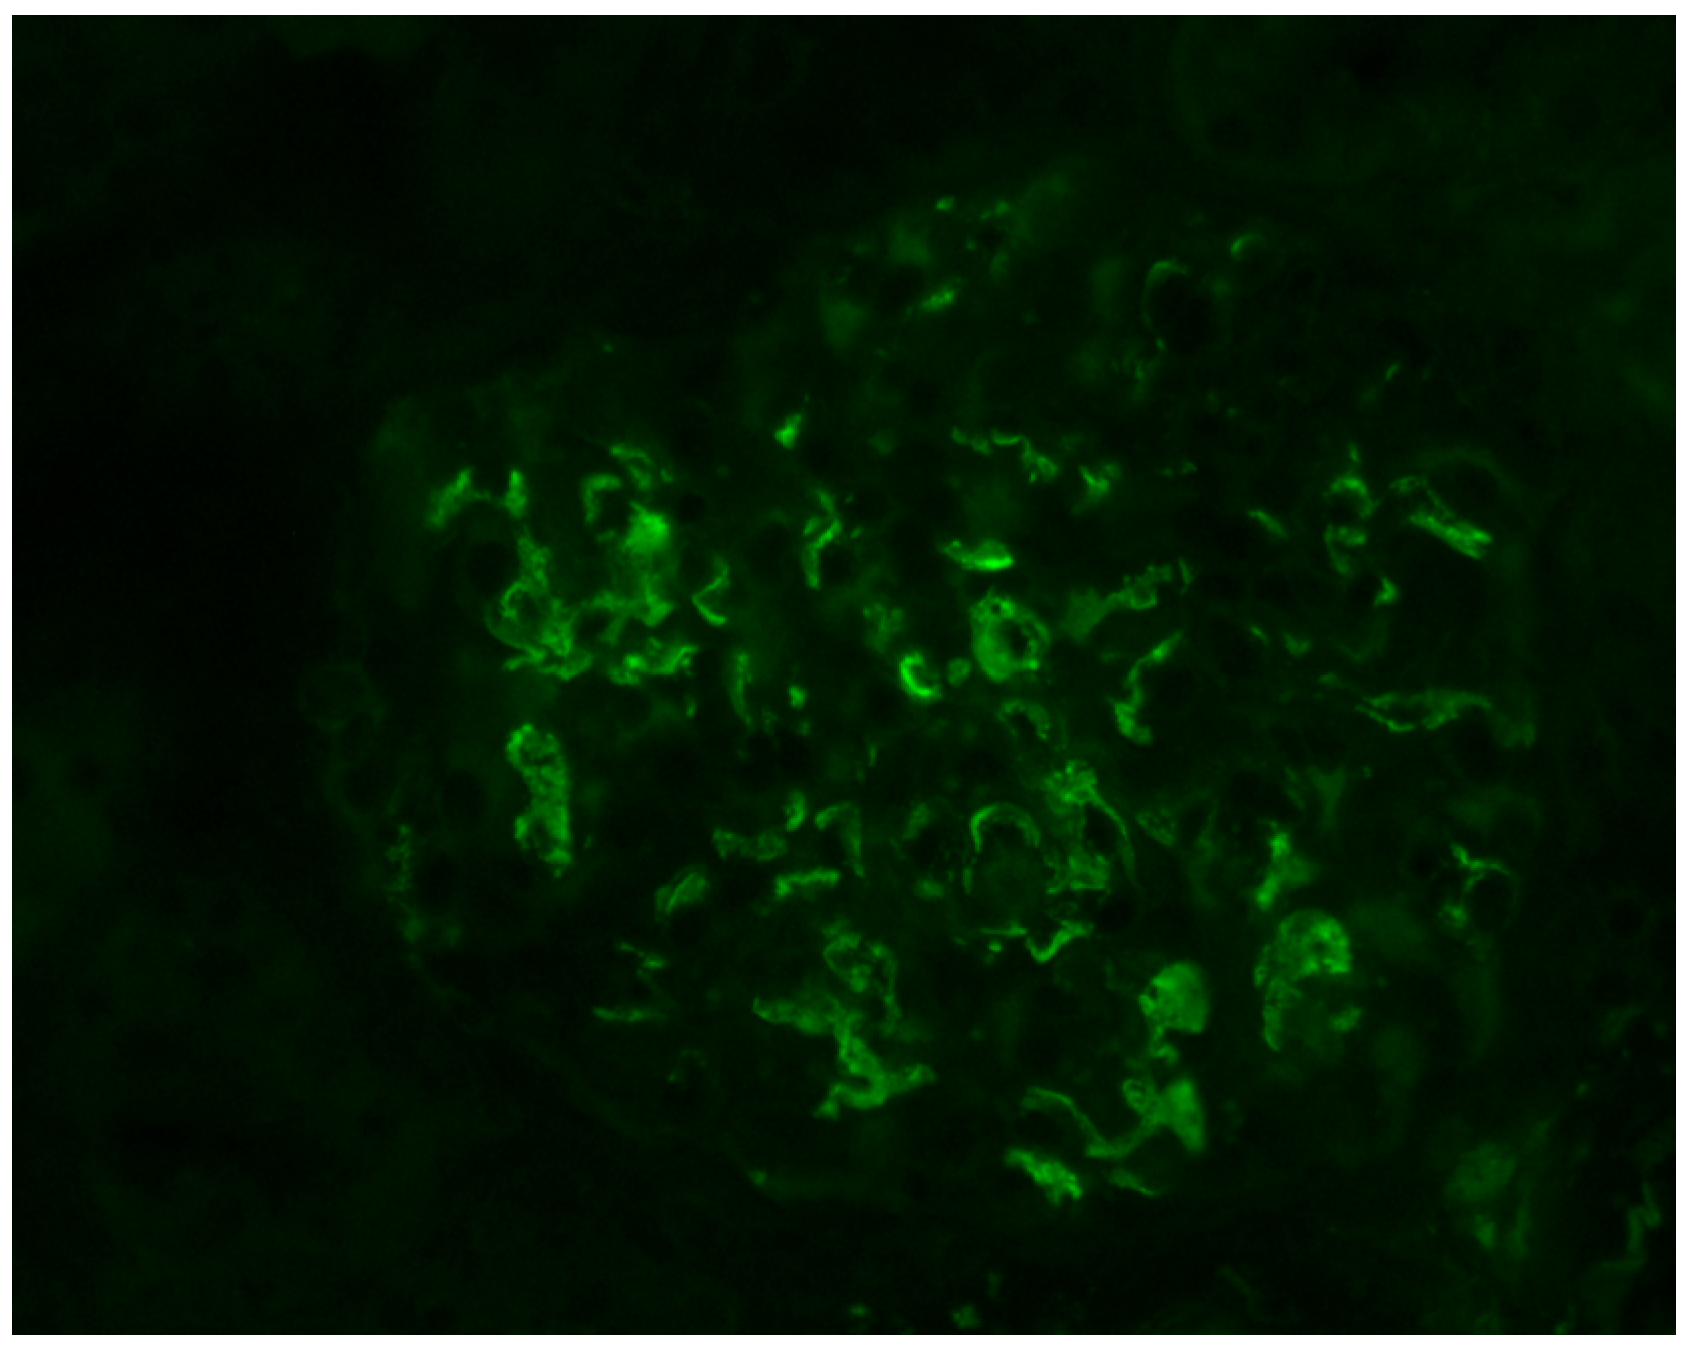

- Berger, J.; Hinglais, N. Intercapillary deposits of IgA-IgG. J. D’urologie Nephrol. 1968, 74, 694–695. [Google Scholar]

- Haas, M. Histologic subclassification of IgA nephropathy: A clinicopathologic study of 244 cases. Am. J. Kidney Dis. 1997, 29, 829–842. [Google Scholar] [CrossRef]

- Cattran, D.C.; Coppo, R.; Cook, H.T.; Feehally, J.; Roberts, I.S.D.; Troyanov, S.; Alpers, C.E.; Amore, A.; Barratt, J.; Berthoux, F.; et al. The Oxford classification of IgA nephropathy: Rationale, clinicopathological correlations, and classification. Kidney Int. 2009, 76, 534–545. [Google Scholar] [CrossRef] [PubMed]

- Roberts, I.S.D.; Cook, H.T.; Troyanov, S.; Alpers, C.E.; Amore, A.; Barratt, J.; Berthoux, F.; Bonsib, S.; Bruijn, J.A.; Cattran, D.C.; et al. The Oxford classification of IgA nephropathy: Pathology definitions, correlations, and reproducibility. Kidney Int. 2009, 76, 546–556. [Google Scholar] [CrossRef] [PubMed]

- Jennette, J.C.; Olson, J.L.; Silva, F.G.; D’Agati, V.D. Heptinstall’ s Pathology of the Kidney, 7th ed.; LWW: Philadelphia, PA, USA, 2015. [Google Scholar]